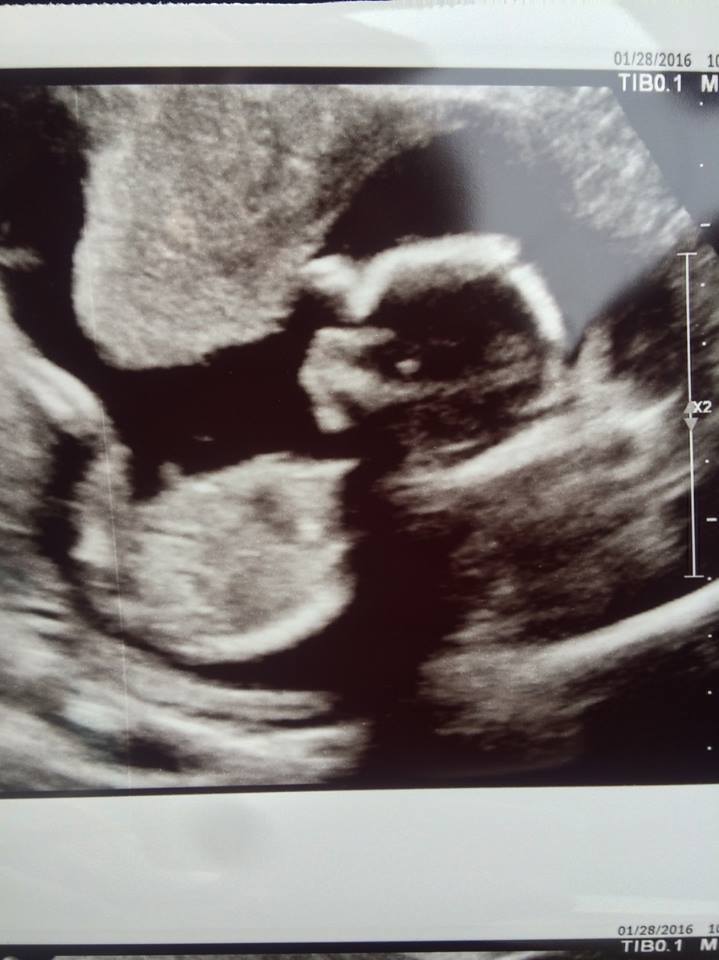

If I lived near DD I could get all the raw milk I wanted. She married a dairy farmer. She is lactose intolerant but she can drink raw milk. She finally got her ultrasound today. They think it is going to be a boy. Still waiting to hear when her due date is. Should be sometime around the end of June beginning of July.